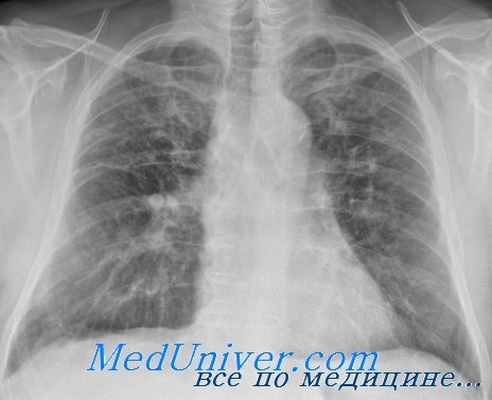

Усиление прикорневого легочного рисунка на рентгене – это симптомокомплекс специфических рентгеновских синдромов в легких, которые свидетельствуют о дыхательной недостаточности, пневмосклерозе легочных полей Рентгенограмма при усилении легочного рисунка с обеих сторон, фиброзные наложение на плевре (обозначены стрелками)

Легочной рисунок – это скопление мелких ветвей легочной артерии, по которым циркулирует кровь по венам и артериям. На рентгенограмме тени не образуют бронхи, лимфатические сосуды. Диаметр легочных сосудов физиологически снижаются в направлении к периферии от корня. Легочной рисунок на рентгеновском снимке интенсивнее прослеживается в периферических отделах легочных полей, где ткани меньше. Калибр кровеносных сосудов небольшой, но рельеф более прослеживается снизу за счет обильного скопления артерий. Усиление прикорневого легочного рисунка в средней зоне наблюдается при хроническом бронхите, бронхиальной астме, туберкулезе, саркоидозе, ряде других патологических форм.